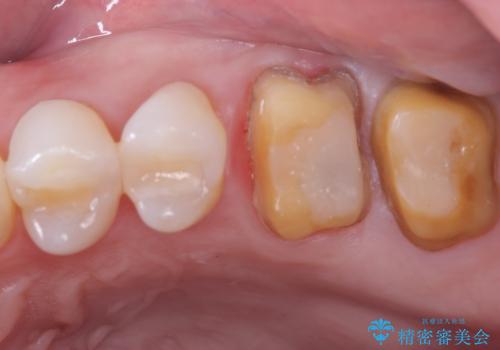

保険適応のメタルインレーと歯質との間に不適合な箇所を認め、補綴物のやり替えでの治療となりました。インレーからクラウンへ補綴物の形態を変更し、素材は清掃性・適合性・審美性の点からセラミッククラウンでのやり替となりました。

健全歯質の残存量から、クラウンでのやり替えを提案しオールセラミッククラウン(スタンダード)でのやり替えとなりました。